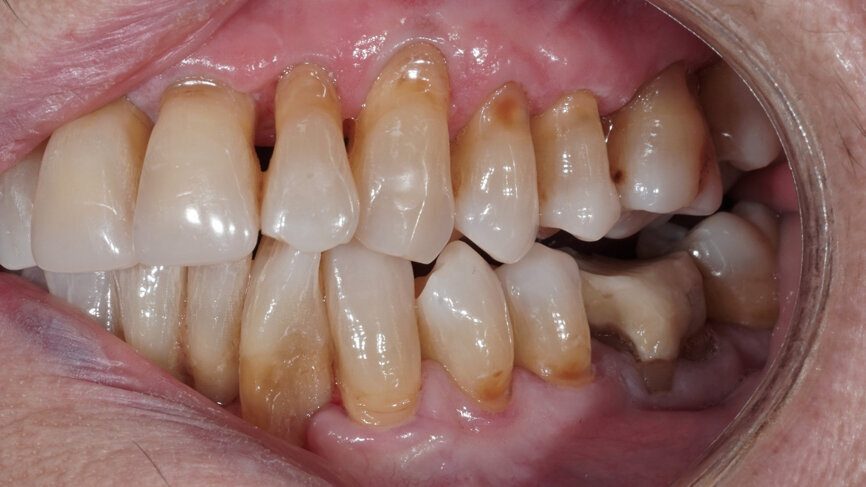

Fig. 2: Clinical situation at the initial appointment in the dental practice.

The 85-year-old female patient presented after osteosynthesis of multiple mandibular fractures she had sustained in a fall (Figs. 1 & 2). During fixation, the left posterior region of the mandible was moved such that teeth #34–37 were brought out of occlusion (Fig. 3). The patient naturally wished to be able to chew properly again in this area. After endodontic treatment of the two avulsed central incisors, which had been replanted in the hospital, and periodontal therapy, occlusal elevation was planned on the left side.